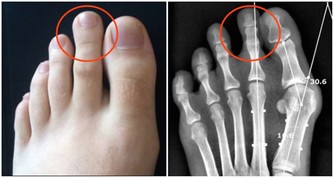

❶、【功能與主治】:滋補肝腎,益精明目。用於虛勞精虧,腰膝痠痛,眩暈耳鳴,內熱消渴,血虛萎黃,目昏不明。 4黃芪